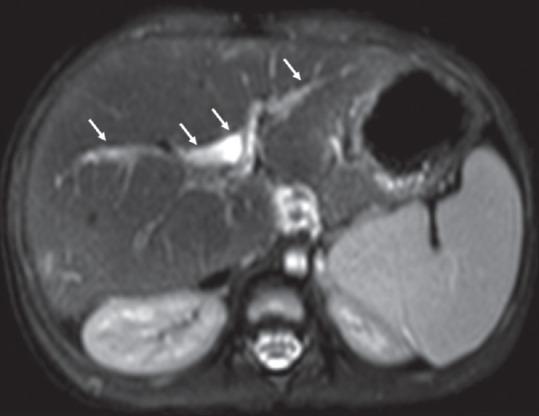

Twenty-one patients were included in the study. The male-to-female sex ratio was 1.6:1, the median age at surgery was 75 days (18-140 days), and the median age at magnetic resonance imaging (MRI) was 4 years (18 months-18 years). More than 2 years of follow-up was in seven patients. Left lobe hypertrophy was observed in six patients, right lobe hypertrophy was in three patients, intrahepatic biliary tract dilatation was in five patients, and altered signal intensity between intrahepatic ducts was seen in five patients. In addition, hypointense foci in the spleen were seen in one patient. Twelve children had normal weight for their age, ten children had the normal height for their age, and gamma-glutamyl transferase was elevated in all children. Only four children had a history of fever and jaundice.

本研究共纳入21例患者。男女比例为1.6:1,手术时的中位年龄为75天(18 - 140天),磁共振成像(MRI)时的中位年龄为4岁(18个月 - 18岁)。7例患者随访时间超过2年。6例患者观察到左叶肥大,3例患者观察到右叶肥大,5例患者观察到肝内胆管扩张,5例患者观察到肝内胆管之间信号强度改变。此外,1例患者脾脏出现低信号灶。12名儿童年龄别体重正常,10名儿童年龄别身高正常,所有儿童的γ-谷氨酰转移酶均升高。只有4名儿童有发热和黄疸病史。

结论

成功手术干预后存活的患者,其MRI/MRCP显示肝脏大体结构接近正常。偶尔可能出现扩张以及叶萎缩/肥大的表现,尤其是有胆管炎病史的患者。存活者的生长参数也在可接受范围内,肝功能正常。